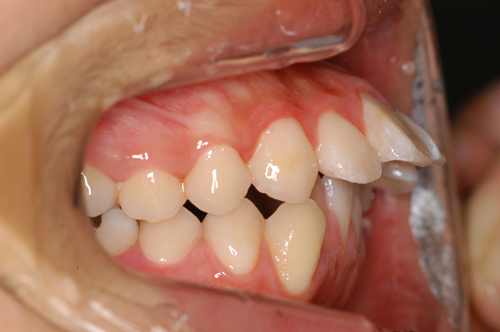

患者:14歳8ヶ月 男性

抜歯部位:上顎、第一小臼歯 下顎第二小臼歯

動的治療期間:18ヶ月